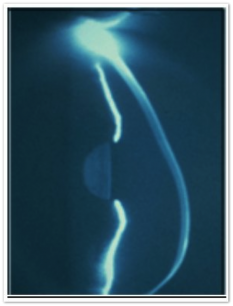

Η AthensLasersight και ο Κ. Σαμαράς έχοντας εκπαιδευτεί σε επίπεδο κλινικού Fellowship στην Αγγλία και την Αμερική στην αντιμετώπιση ενός ευρέως φάσματος ασθενειών που επηρεάζουν το μπροστινό μέρος του ματιού εξειδικεύεται στη θεραπεία παθήσεων του κερατοειδούς.